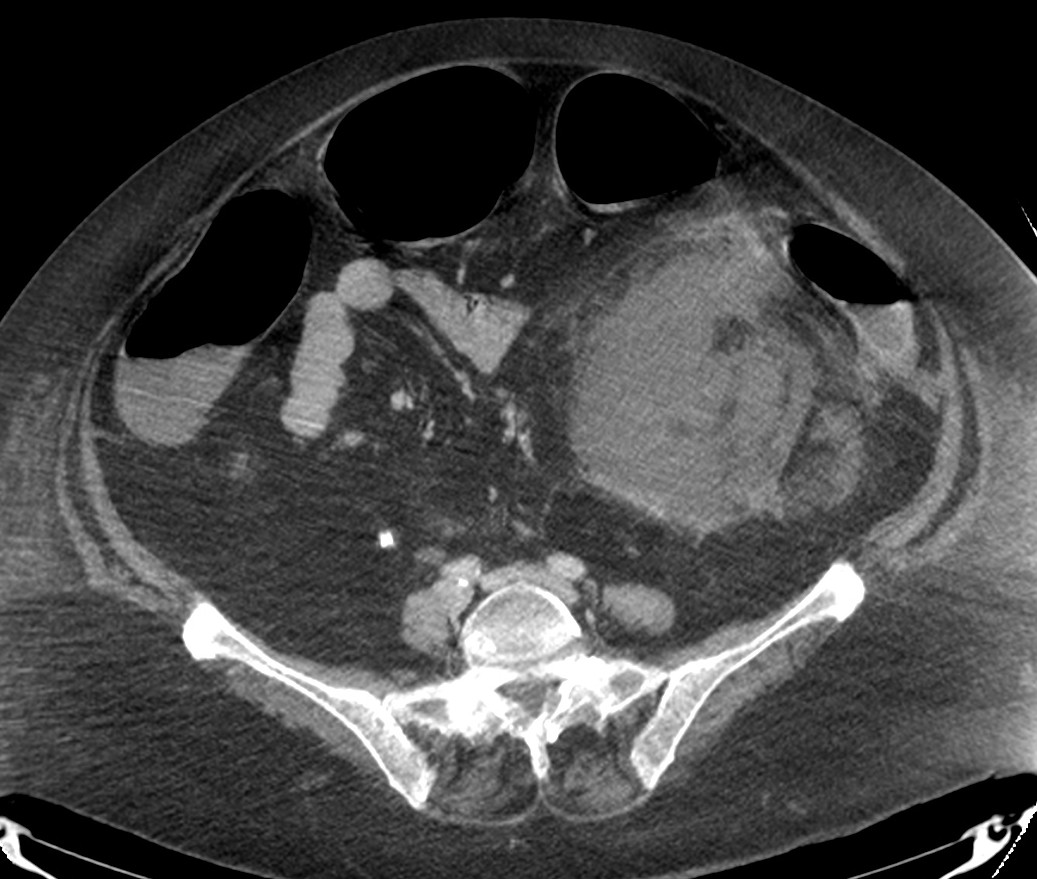

Paciente mujer de 62 años que acude por decaimiento general con fiebre y dolor en flanco izquierdo. Ingresa en UVI por signos de sepsis

Nos cuenta antecedentes de pielonefritis e hidronefrosis crónica.

Hallazgos en imagen:

Estos hallazgos pueden ser dificiles de interpretar, ya que una paciente con hidronefrosis crónica y litiasis en el uréter puede haber sufrido una obstrucción que origina un cuadro de dolor en FRI con ruptura de cálices y colección extra axial. Otra probabilidad puede ser un angiomiolipoma que ha roto un aneurisma y ha producido un sangrado. También podríamos estar ante una pionefrosis aunque dada dada la clínica, los antecedentes y al observar los hallazgos en TC podríamos establecer la sospecha de pielonefritis xantunogranulomatosa con alta probabilidad. La confrimación vendrá dada con la nefrostomía y estudio de anatomía patológica.